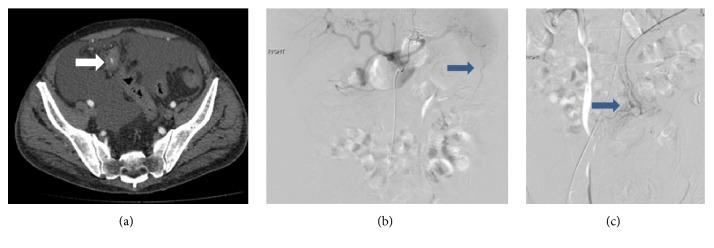

Trans Arterial Embolization of Spontaneous Intra-Abdominal Haemorrhage from Omental Lipoma.

We describe 3 cases of omental lipoma of whom 2 presented with symptomatic haemorrhage. Notably the haemorrhage in the 2 reported cases was from foregut arteries. Thorough knowledge of anatomy and embryology is critical in identifying the source of haemorrhage and differentiating this condition from other common causes of mesenteric haemorrhage. To the best of our knowledge, this is the first case series reporting this uncommon cause for abdominal haemorrhage. The successful management of this condition using superselective embolization is discussed. Clinicians need to exercise diligence and caution in omental lipomas presenting with spontaneous haemorrhage and this notion is exemplified in our reported cases.

我们描述了3例网膜脂肪瘤病例,其中2例出现症状性出血。值得注意的是,在这2例报告病例中,出血来自前肠动脉。全面了解解剖学和胚胎学对于确定出血来源以及将这种情况与肠系膜出血的其他常见原因区分开来至关重要。据我们所知,这是首个报告这种罕见的腹部出血原因的病例系列。本文讨论了使用超选择性栓塞成功治疗这种疾病的方法。对于出现自发性出血的网膜脂肪瘤,临床医生需要勤勉谨慎,我们报告的病例就体现了这一点。